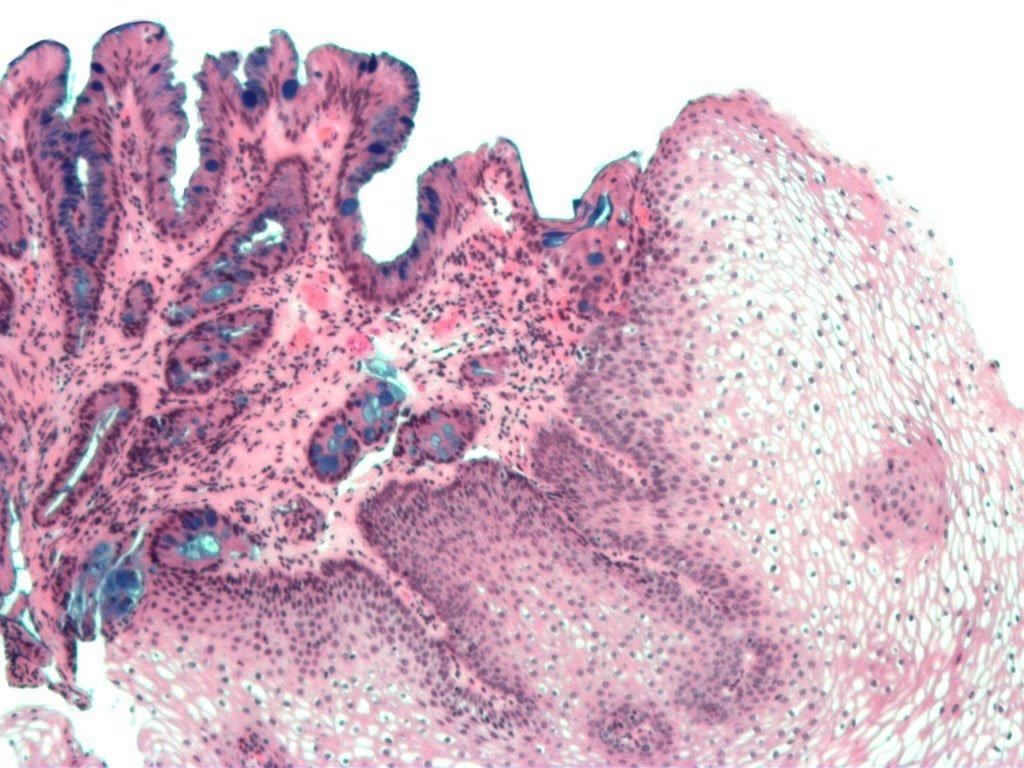

Dinding kerongkongan tersusun atas sel-sel rata dan pipih yang disebut sel skuamosa. Paparan asam secara terus-menerus dapat mengikis sel skuamosa dan mengubahnya menjadi sel kolumnar yang mirip dengan sel-sel pada dinding lambung.

Saat bentuk sel telah berubah itulah yang disebut sebagai Barrett’s esophagus. Kondisi ini berkaitan dengan meningkatnya risiko kanker esofagus.

Jaringan kerongkongan yang normal akan tampak pucat dan mengilap. Sementara itu, jaringan kerongkongan yang mengalami kerusakan tampak kemerahan dengan tekstur seperti beludru.

Dokter juga dapat melakukan pengambilan sampel jaringan (biopsi) pada pemeriksaan yang sama. Hasil biopsi akan menunjukkan tingkat keparahan penyakit dan apakah ada tanda-tanda jaringan kanker.